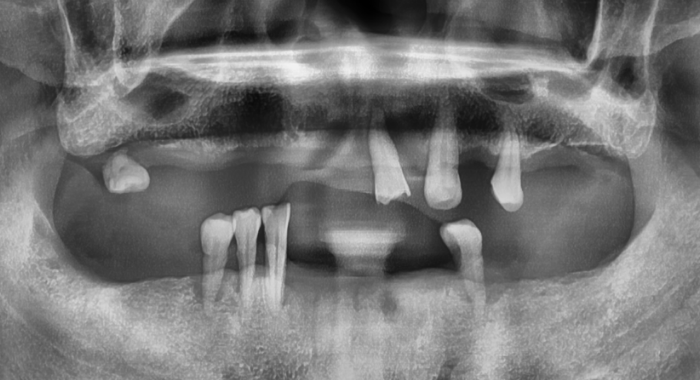

자연치아를 보존하는 것이 가장 좋지만, 불가능하다면 정확한 진단과 정밀한 시술로

내 치아처럼

오래 사용할 수 있는 임플란트를 선택해야 합니다.

CT와 스캐너 기반의 정밀한 디지털 시술

CT와 스캐너 기반의 정밀한 디지털 시술로, 신경 손상 없이 빠르고 정확하게.